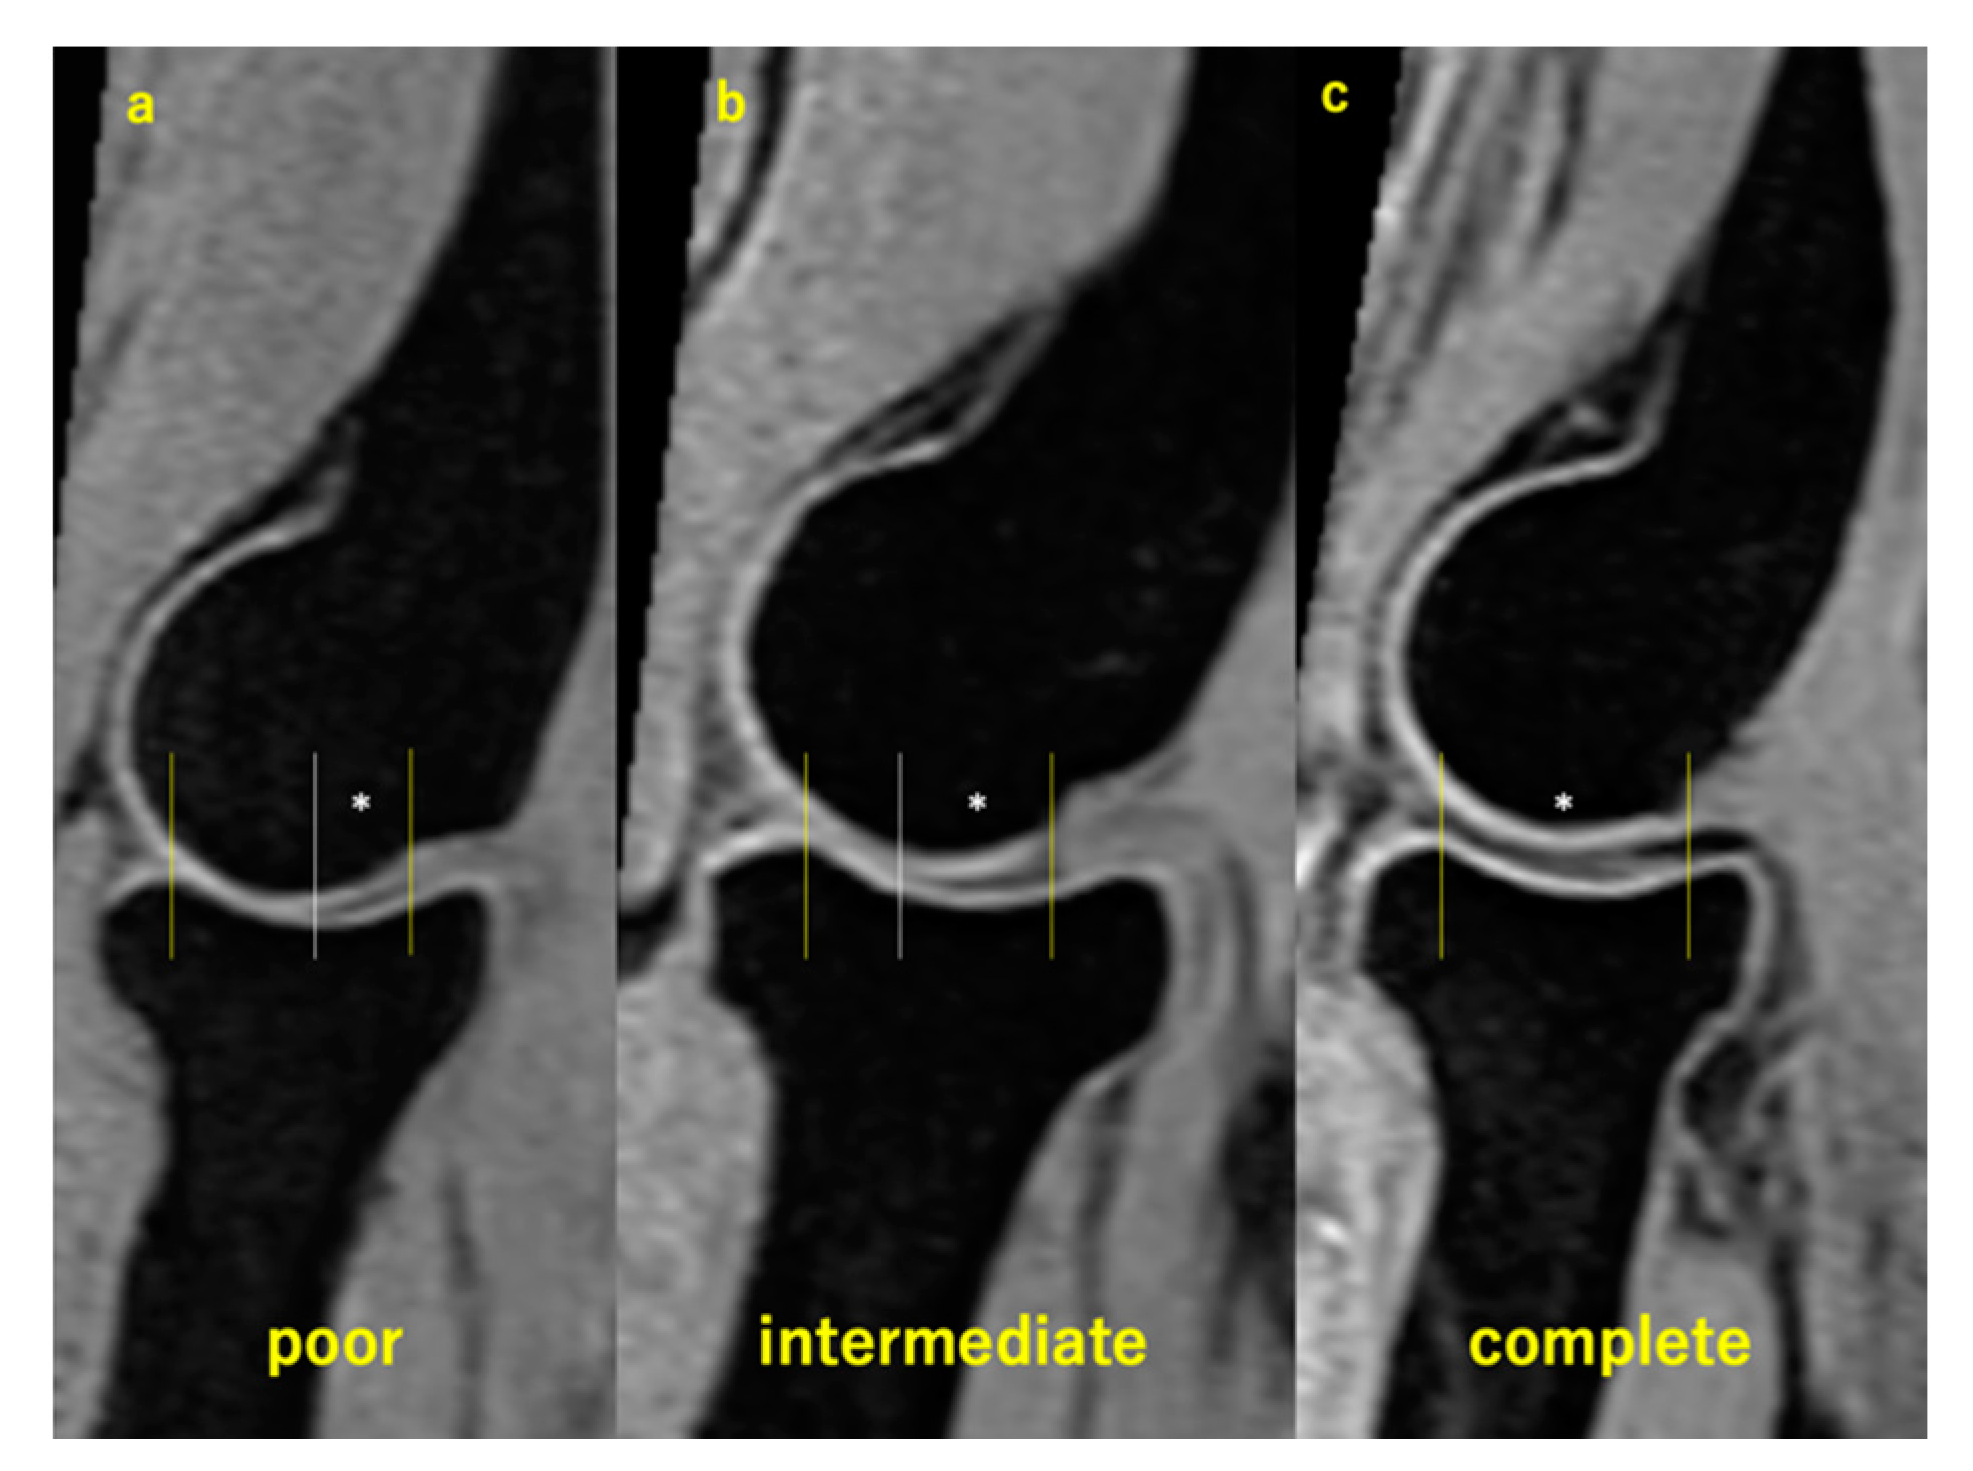

2.6. Assessment of HACOV